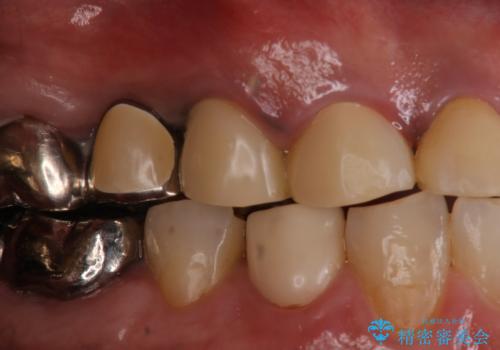

歯肉からの出血 適合の悪い銀歯をオールセラミックのブリッジにやり替え

- 右上奥歯の歯肉から出血があり異和感をおぼえ来院された患者様です。

以前の被せ物を除去し、仮歯に変えてすぐに異和感がとれました。

歯周治療を行い、歯肉が引き締まってから補綴治療しました。